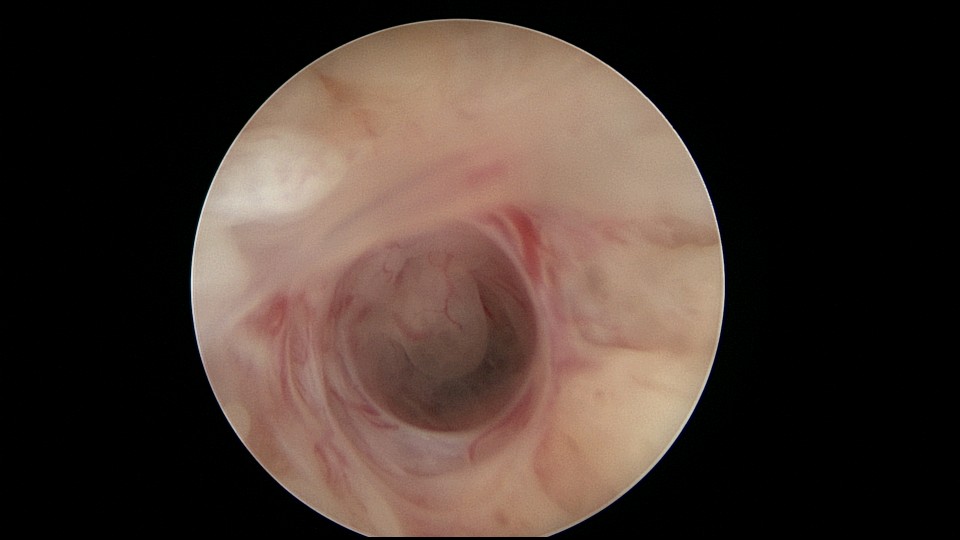

患者25岁,G1P0,停经52天,稽留流产,B超宫内偏右查见大小约2.4cmx1.0cmx1.7cm孕囊回声,形态规则,内可见直径约0.4cm的卵黄囊回声,未见胎芽,孕囊旁肌层最薄处厚约0.5cm,子宫中下段回声连续性欠佳,似可见一分隔回声。2021年7月宫腔镜探查,胚胎着床于宫腔前壁偏右,宫颈内口及宫腔左侧壁粘连。清除妊娠组织,单极电针分粘,恢复宫腔形态,双侧输卵管开口显露(第一次怀孕,宫腔粘连原因?)。2022年7月自然妊娠,2023年3月足月剖宫产分娩。2024年12月,外院人流术后1+月,宫内残留,与后壁肌层分界欠清,局部血流信号增多,到我院宫腔镜切除残留组织(后3张图片)。现患者30岁,G3P1。宫腔粘连常常不能阻止妊娠,但胚胎停育发生率增加。